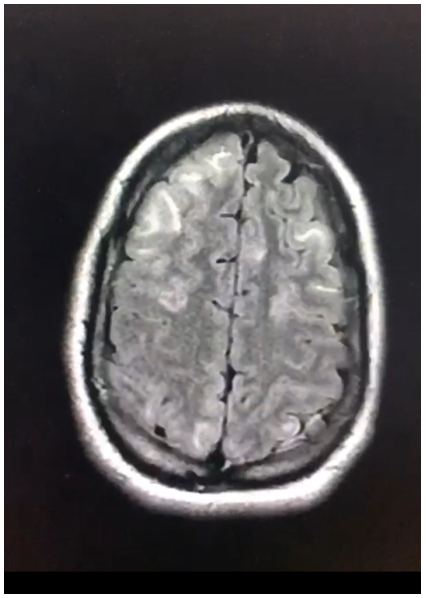

Posterior Reversible Encephalopathy Syndrome (PRES) Secondary to an Eclampsia Episode: A Report of Case

Moad Belouad, Abdelhamid Benlghazi, Ahmed Fakri, Saad Benali, Hamza Messaoudi, MLY Mehdi Elhassani and Jaouad Kouach. 13(9): 01-05.